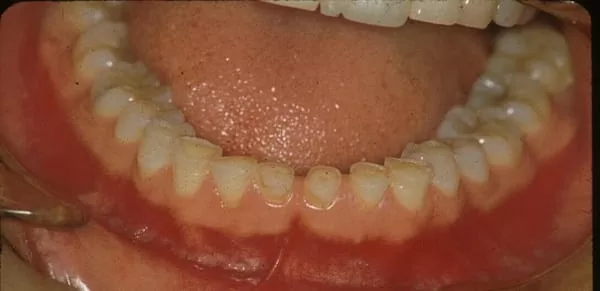

圖說: 磨牙者牙齒嚴重磨耗情形